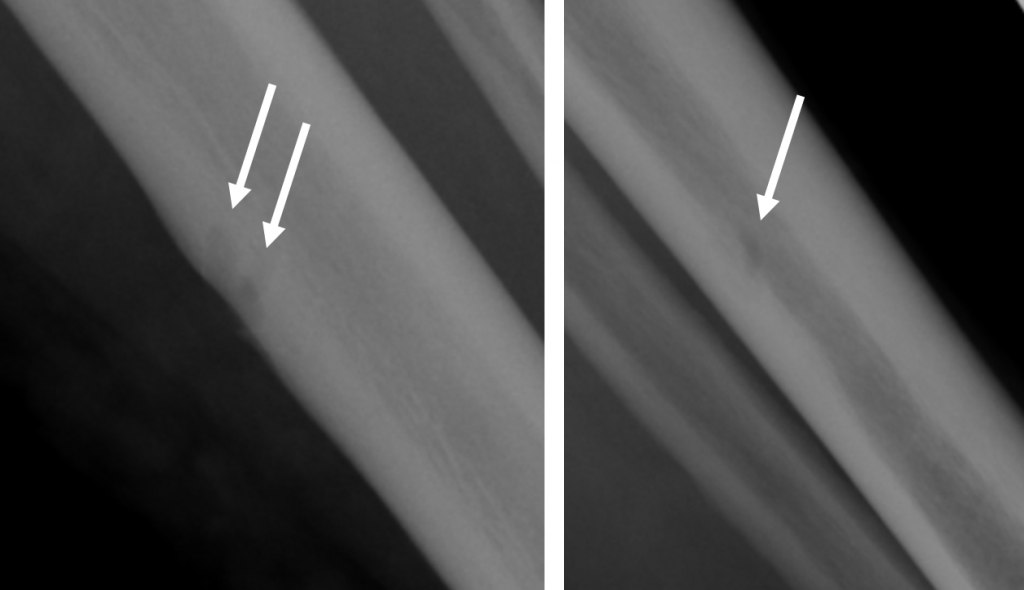

- Ausgeprägte Tenosynovitiden, v.a. der Flexorensehnen (Pfeile) (T1 FS KM)

- Diffuses Weichteilödem entlang des 5. Strahles mit korrespondierender KM- Aufnahme (Pfeile) (T1 FS KM)

- Zusätzliche diffuse ödematöse Veränderungen im Subkutangewebe der gesamten Hand (Pfeile) mit fehlender oder nur sehr wenig korrespondierender KM Aufnahme